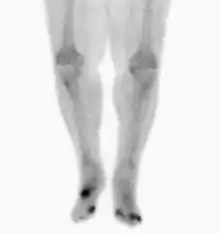

Osteomyelitis in both feet as seen on bone scan

Nuclear medicine scans can be a helpful adjunct to MRI in patients who have metallic hardware that limits or prevents effective magnetic resonance. Generally a triple phase technetium 99 based scan will show increased uptake on all three phases. Gallium scans are 100% sensitive for osteomyelitis but not specific, and may be helpful in patients with metallic prostheses. Combined WBC imaging with marrow studies has 90% accuracy in diagnosing osteomyelitis.[26]